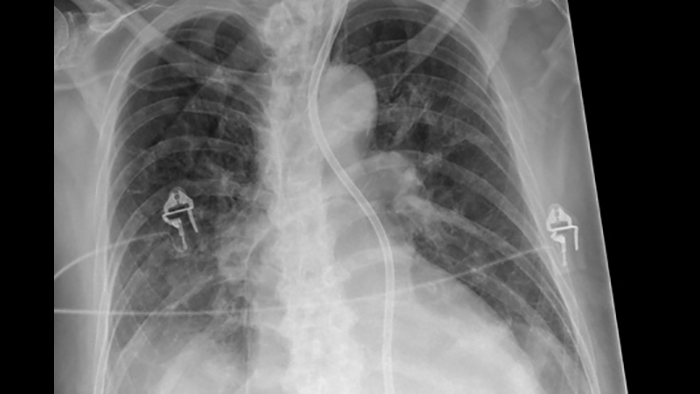

When doing DR exams without a grid, Philips SkyFlow Plus produces images with grid-like contrast. It reduces the effect of scattered radiation for non-grid bedside chest exams. SkyFlow Plus is the industry’s first scatter correction algorithm for portable X-rays. It delivers contrast enhancement based on the amount of scatter for the individual patient.